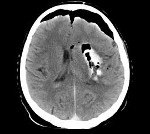

Поскольку пневмоцефалия не имеет специфических клинических проявлений и в половине случаев наблюдается ее субклиническое течение, то диагностировать ее клинически неврологу и нейрохирургу практически невозможно. Интракраниальное наличие воздуха может быть выявлено при рентгенографии черепа. Для диагностики основной патологии, определения локализации и размеров воздушного пузыря целесообразно проведение КТ или МРТ головного мозга. КТ головного мозга выявляет субдуральное, интравентрикулярное или внутрицеребральное скопление воздуха (воздушную кисту), может наблюдаться феномен «воздушного колокола». Инфекционная пневмоцефалия отличается наличием на томограммах перифокального воспаления.